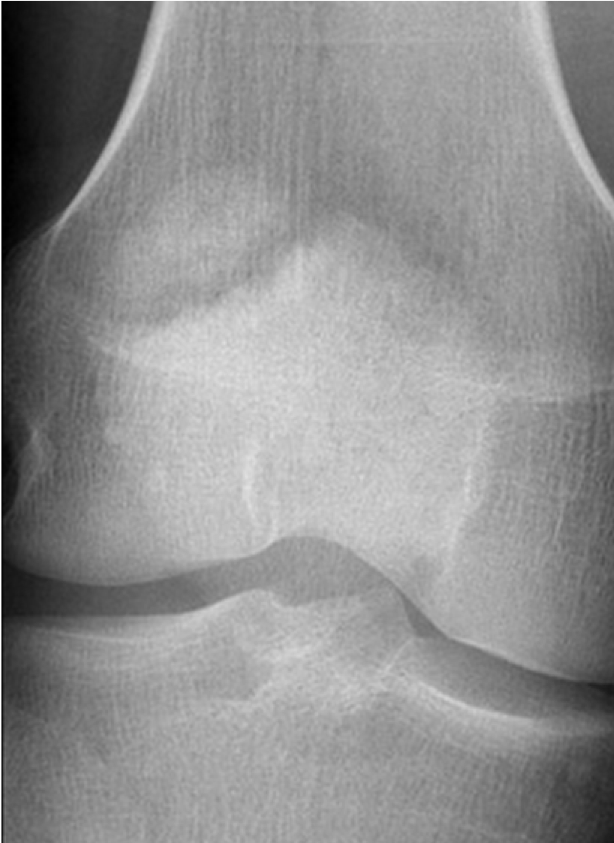

This 75 year old woman presented with difficulty walking and knee pain. How would you describe these X-rays?